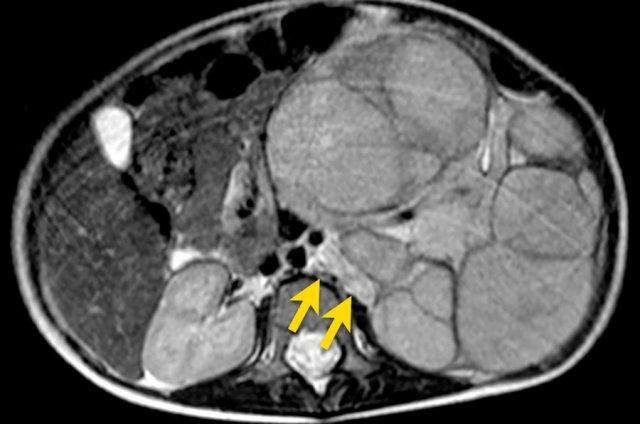

Ví dụ 1

Một bé gái ba tuổi có khối u thận trái và huyết khối khối u lớn trong tĩnh mạch thận và tĩnh mạch chủ dưới. Có di căn gan (phát hiện không thường gặp) và di căn phổi.

A. The tumor enhances less than the peripheral remnant of normal renal tissue (blue arrow). The left renal vein is open (yellow arrow). Solid parts of the tumor show diffusion restriction (white arrow)

U nguyên bào thận thường không đồng nhất, với tín hiệu giảm trên T1 và tín hiệu tăng trên T2. Các vùng hoại tử dạng nang thường hiện diện.

Tăng cường tín hiệu sau tiêm Gadolinium không đồng nhất và kém hơn so với sự tăng cường của nhu mô thận bình thường.

Các phần đặc của khối u sẽ cho thấy khuếch tán hạn chế. Xuất huyết thường gặp. Các vùng xuất huyết cũng sẽ cho thấy khuếch tán hạn chế, vì vậy hãy quan sát trên hình ảnh T1 để tìm dấu hiệu chảy máu.